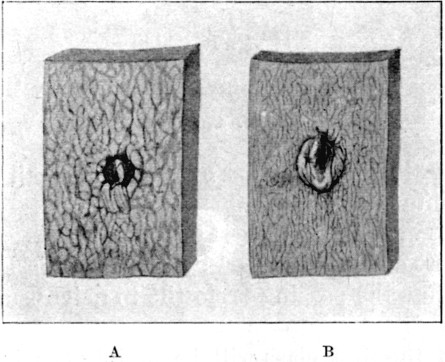

16. Entry and Exit Mauser Wounds56

25a. Sections of Mauser Entry and Exit Wounds74